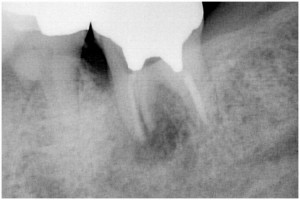

左下奥歯根破折